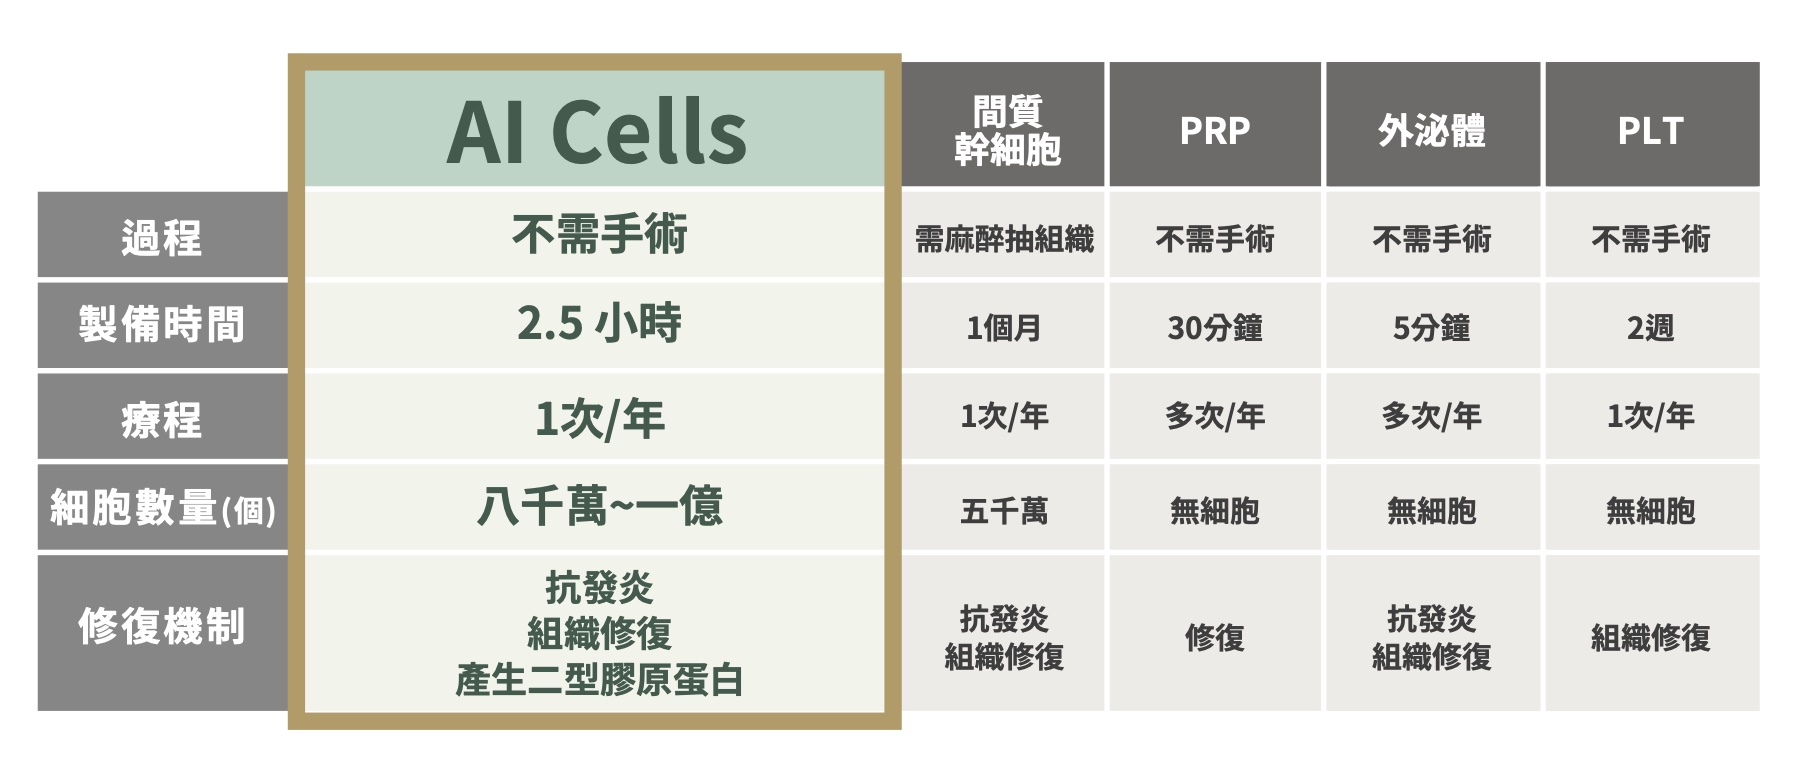

AI Cells 與其他療法比較表

依照比較表內容,AI Cells 的特色可整理為:療程過程不需手術、製備時間約 2.5 小時、通常 1 次/年療程、細胞數量約八千萬至一億,並具有抗發炎、組織修復與產生二型膠原蛋白等修復機制。

相較之下,間質幹細胞需麻醉抽組織,製備時間約 1 個月,細胞數量約五千萬;PRP、外泌體與 PLT 雖多數不需手術,但 PRP 製備時間約 30 分鐘、外泌體約 5 分鐘、PLT 約 2 週,且多屬無細胞或不同修復概念。若以療程便利性、製備時間、細胞數量與修復機制來看,AI Cells 在退化性疾病與疼痛治療中具備相對鮮明的差異化特色。